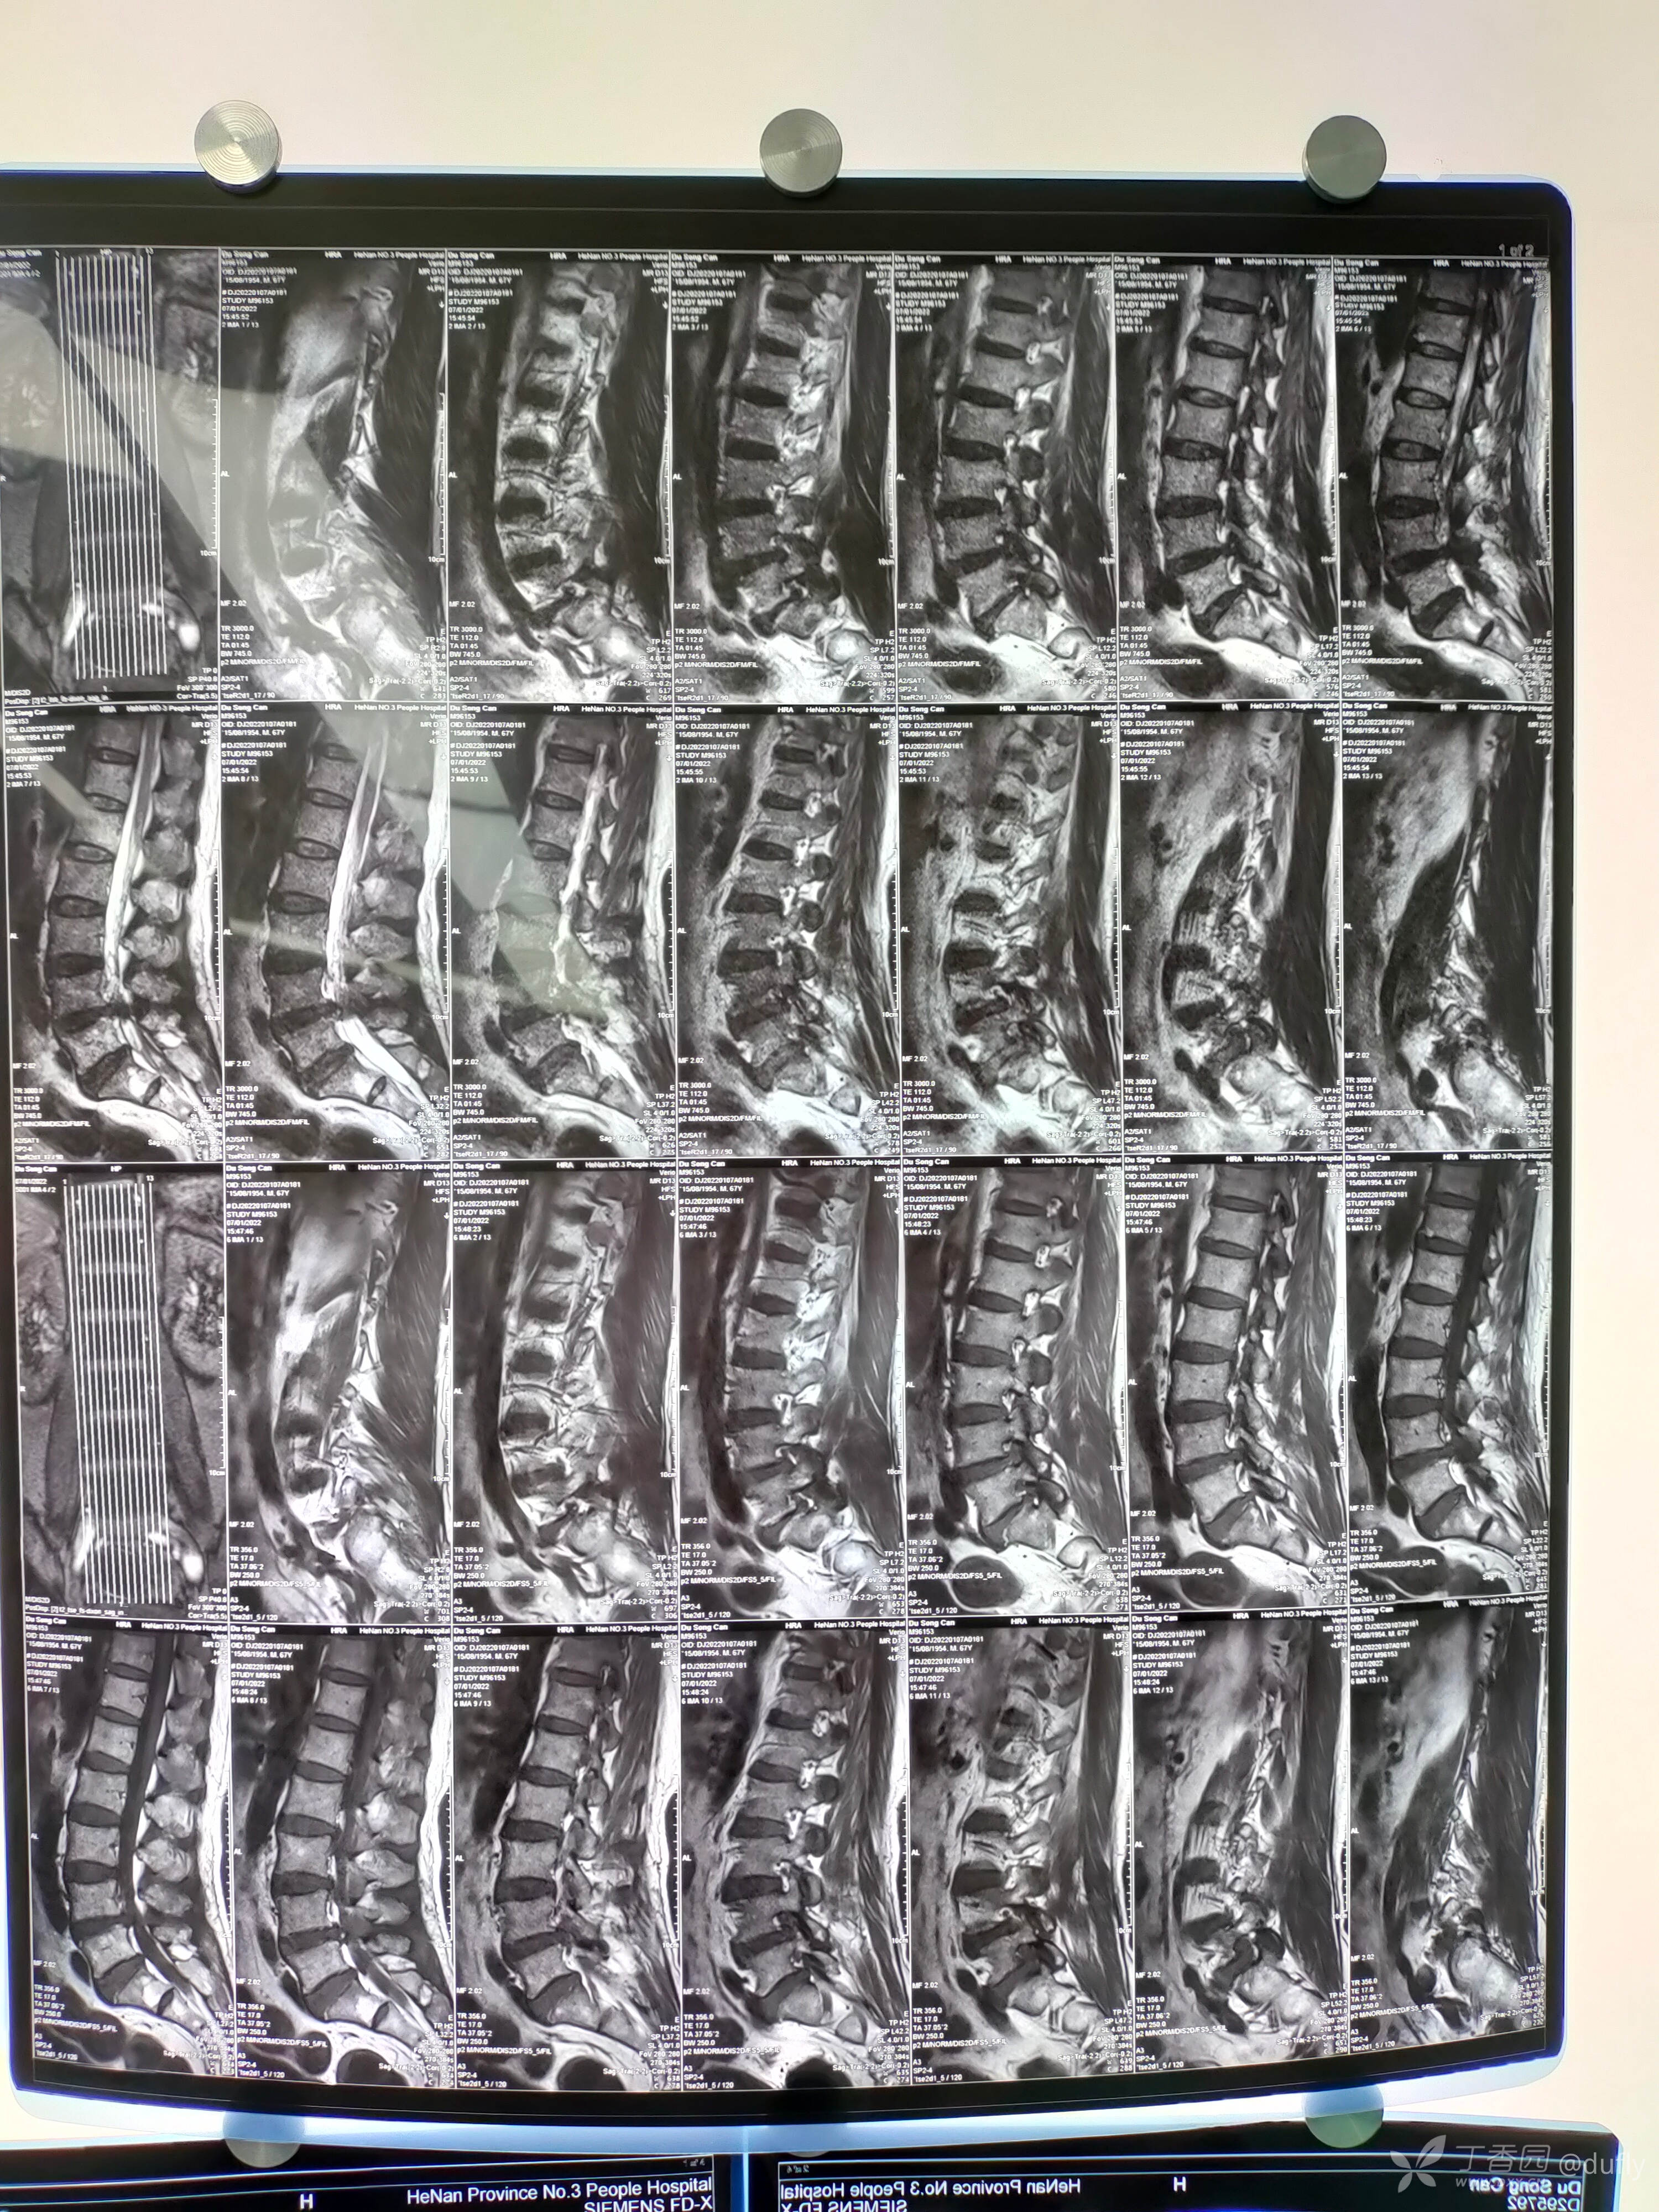

腰椎核磁:腰45重度椎管狭窄。腰5骶1左侧极外侧突出。

初步诊断:腰椎管狭窄症(L4/5),腰椎间盘突出症(L5/S1,左侧,极外侧)。

手术方案:经椎间孔入路内镜下取出腰5/骶1极外侧的髓核,再经椎间孔入路,完成腰45减压。

因为腰5骶1是极外侧突出,所以减压靶点是椎间孔上部,显露出口根。穿刺到骶1上关节突肩部,去除上关节突肩部和腹侧骨质,向头端分离,取出出口根下方的髓核。发现两块较大的突出髓核。

再经椎间孔入路处理腰45的腹侧压迫。椎间盘后缘突出钙化,在去除部分关节突以后,显露行走根和硬膜囊。

完成腹侧的减压。在咬除硬膜腹侧骨化的突出椎间盘的时候有很大的困难。其中发生止血困难两次。每次止血时间都超过10分钟。最后减压至1区,没有充分减压到对侧。